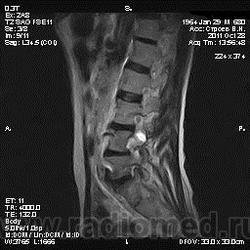

Жалобы на боли в пояснице постоянного характера, исследование началось после приема обезболивающего препарата, предоставлены выписки после неоднократного лечения в стационаре с диагнозом: Полисегментарный остеохондроз, деформирующий спондилез, грыжа диска L4-5, протрузия диска L3-4, умеренно выраженный болевой синдром.

От оперативного лечения отказался по поводу эпиприступов в анамнезе.

По структуре и локализации образование, вероятно, исходящее из корешков спинного мозга. Как у него с тазовыми функциями?

То что видно -слишком гомогенный сигнал для дермоида. Учитывая деформацию костных структур- заболевание существует давно. И не забыть внимательно посмотреть на предмет spina bifida, может это вообще грыжа. Контрастику бы налить.

я за невриному , структура гомогенная , а дермоид , неоднороден и выглядит как "губка", то есть с мелкими очагами повышенного мр-сигнала в Т2. по- моему...

вообще то забираю свои слова обратно (не согласна с невриномой) ... одолели сомнения.. там кажется есть кистозный компонент , отличный от сигнала спинномозговой жидкости . гистология покажет ))

Кистозный компонент не исключает невриному.

в литературе говорится что экскавация или продавливание задней поверхности позвонка- тоже характерная черта роста неврином в этой локализации.